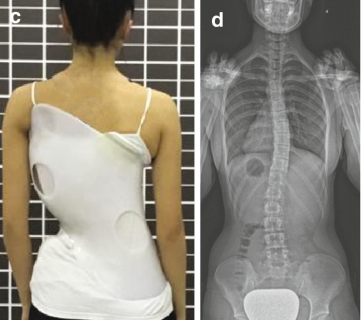

واحدة من أكثر طرق العلاج غير الجراحية شيوعًا هي ارتداء حزام اعوجاج العمود الفقري، المعروف طبيًا باسم TLSO الذي يساعد على تقويم العمود الفقري ومنع زيادة الانحناء. ومع ذلك، كثير من الأهالي يتساءلون: هل الحزام فعّال حقًا؟ كم ساعة يجب أن يرتديه الطفل يوميًا؟ وهل ارتداء الحزام يقلل من خطر الحاجة للجراحة لاحقًا؟

التطور الكبير في تصميم الأحزمة الطبية جعل علاج اعوجاج العمود الفقري عند المراهقين أكثر نجاحًا وأقل إزعاجًا. باستخدام تقنيات التصوير الثلاثي الأبعاد والمحاكاة الرقمية، أصبح الحزام أكثر خفة وراحة، ويعطي نتائج أفضل في تصحيح الانحناء والتواء العمود الفقري.